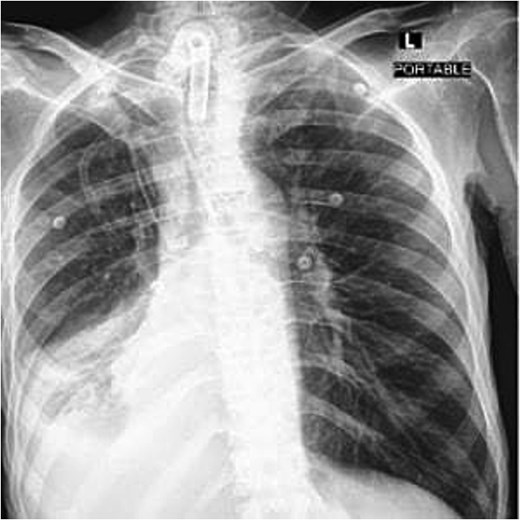

A 40-year-old male who is known to have amyotrophic lateral sclerosis was admitted to the intensive care unit for ventilatory support. He underwent surgical tracheostomy for long-term mechanical ventilation dependence, a double-lumen tracheostomy tube with an internal diameter of 8 mm and a maximum cuff pressure of 25.4 mm was inserted, post-operative chest X-ray confirmed tube placement (Fig. 1). Six months later, the otolaryngologist on-call was consulted regarding ventilation leak that was evident in the ventilator. Flexible endoscopy through the stoma revealed a significantly dilated trachea with a posterior groove. The tube was changed to size 7 with an extended distal length of 49 mm to bypass the dilated segment. A temporary improvement was noted; however, the leak was noted again, with an inspiratory tidal volume of 800, and an expiratory volume of 135, the cuff pressure was gradually elevated to overcome the leak reaching a maximum of 40 mmHg, with the cuff seen over-inflated in routine supine chest X-ray (Fig. 2). Multiple tube obstruction events happened later, which required rigid bronchoscopy examination under general anesthesia to assess and relieve the obstruction. Intraoperative examination revealed that the obstruction was caused by a large dry blood clot, withdrawal of the tube to examine the trachea further revealed a large posterior tracheal wall defect with exposed thoracic vertebrae. The patient underwent a subsequent contrast-enhanced computed tomography scan (CECT) of the neck and chest which confirmed the intraoperative findings (Fig. 3). The leak was not improving by increasing cuff pressure, consequently, the decision was made to use an armored endotracheal tube size 8 at a lip level of 13 to bypass the defect. This has slightly improved the oxygenation and ventilation of the patient, but it did not eliminate the leak. The general poor health of the patient along with his do-not-resuscitate (DNR) status has led to deterring the decision of surgical tracheal wall repair. The patient was further diagnosed with sepsis due to multiple infection sources including his long-term suprapubic urinary catheter, he eventually had a cardiopulmonary collapse a few weeks later and passed away.

Frontal portable chest radiograph showing a tracheostomy tube in satisfactory position above the carina, however, there is a rounded radiolucency at the expected position of the tracheostomy cuff suggestive of tracheostomy tube cuff overinflation. Additionally, there is a small right pleural effusion with adjacent atelectatic changes/ consolidation.